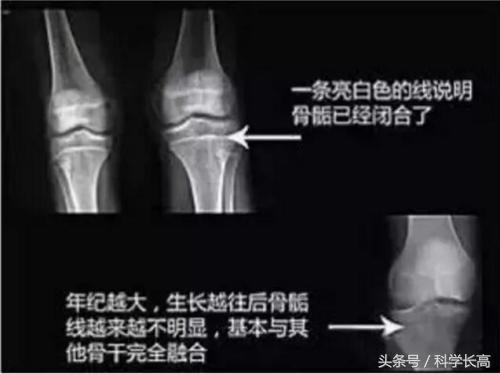

青春期是由于下丘脑-垂体-性腺轴苏醒,性激素分泌增加,生长速度加快。男孩最早出现的增大,女孩乳腺增大首先出现。生长的速度每年都在6厘米以上。女孩初潮出现以后,往往半年到一年骨骺线闭合,青春期结束。男孩出现、腋毛,喉结增大,声音变粗低沉,也会出现遗精的情况。经过五年左右,男孩、女孩都具备了生殖的能力,第二性征发育成熟,同时骨骺线都闭合,达到了成年终身高。

谢邀,先普及一下知识,决定未来身高主要看骨龄而不是年龄:一般来说18岁男孩骨龄刚刚闭合,长骨就长不了了,但脊椎骨还有3年左右才完全闭合,也就是说18岁男孩可以做拉伸摸高吊扛等运动让自己多长二分。当然这是骨龄与年龄一样的情况下,如果是骨龄小,发育迟缓的孩子,骨骺线还没闭合,长骨也能长,脊柱也能长,但如果骨龄大,脊柱闭合时间短,长幅就更小了。